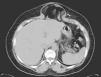

Preparación preoperatoria y protocolo de tratamientoTodos los pacientes han sido estudiados mediante TAC dinámica de la región (fig. 1) practicada con maniobra de Valsalva, para valorar diámetros y volumen del defecto, sus relaciones y el contenido del saco8; este detalle técnico ofrece valiosa información.